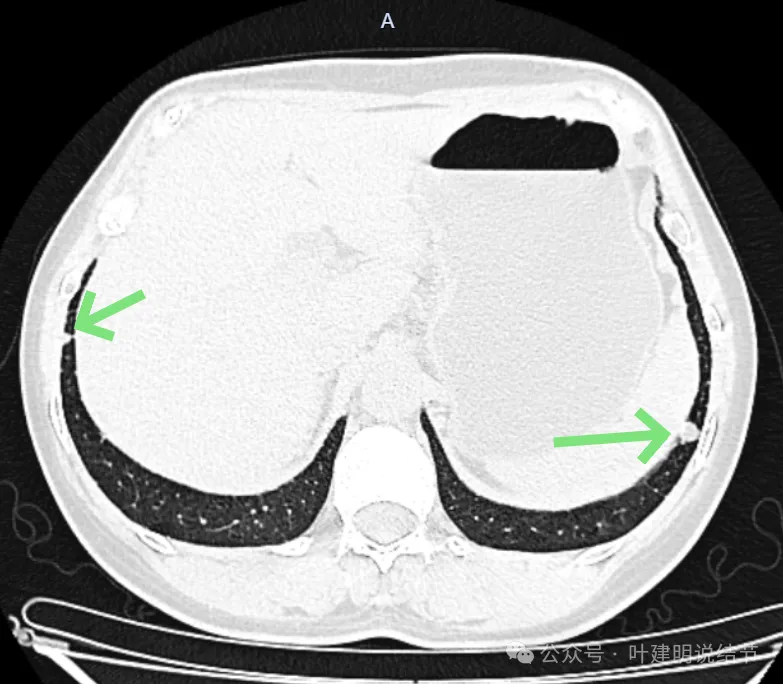

先来看2024年10月16日的影像:

右上后段混合密度结节,瘤肺边界欠清,有明显实性成分,边缘不光滑。

左下叶混合密度结节,边缘有淡的磨玻璃影,瘤肺边界欠清,实性成分明显,略偏散。

再看2024年9月27号体检时右上后段与左下最明显两处以及实性结节处的影像:

右上与左下混合密度的病灶当时都没有,实性结节是有的。

蓝色的是实性的小结节,缺乏膨胀性,两次检查都有,没有变化,考虑是良性的;红色的这些事10月份检查新增的,这两处比较明显的9月份的时候就是绿色框起来这个区域,当时是没有的。短时间内出现、多发病灶、边缘模糊、轮廓欠清,没有恶性特征,与炎性病变符合。建议查查隐球菌方面的化验,如此结果阳性,请呼吸内科或感染科处理。意见供参考!